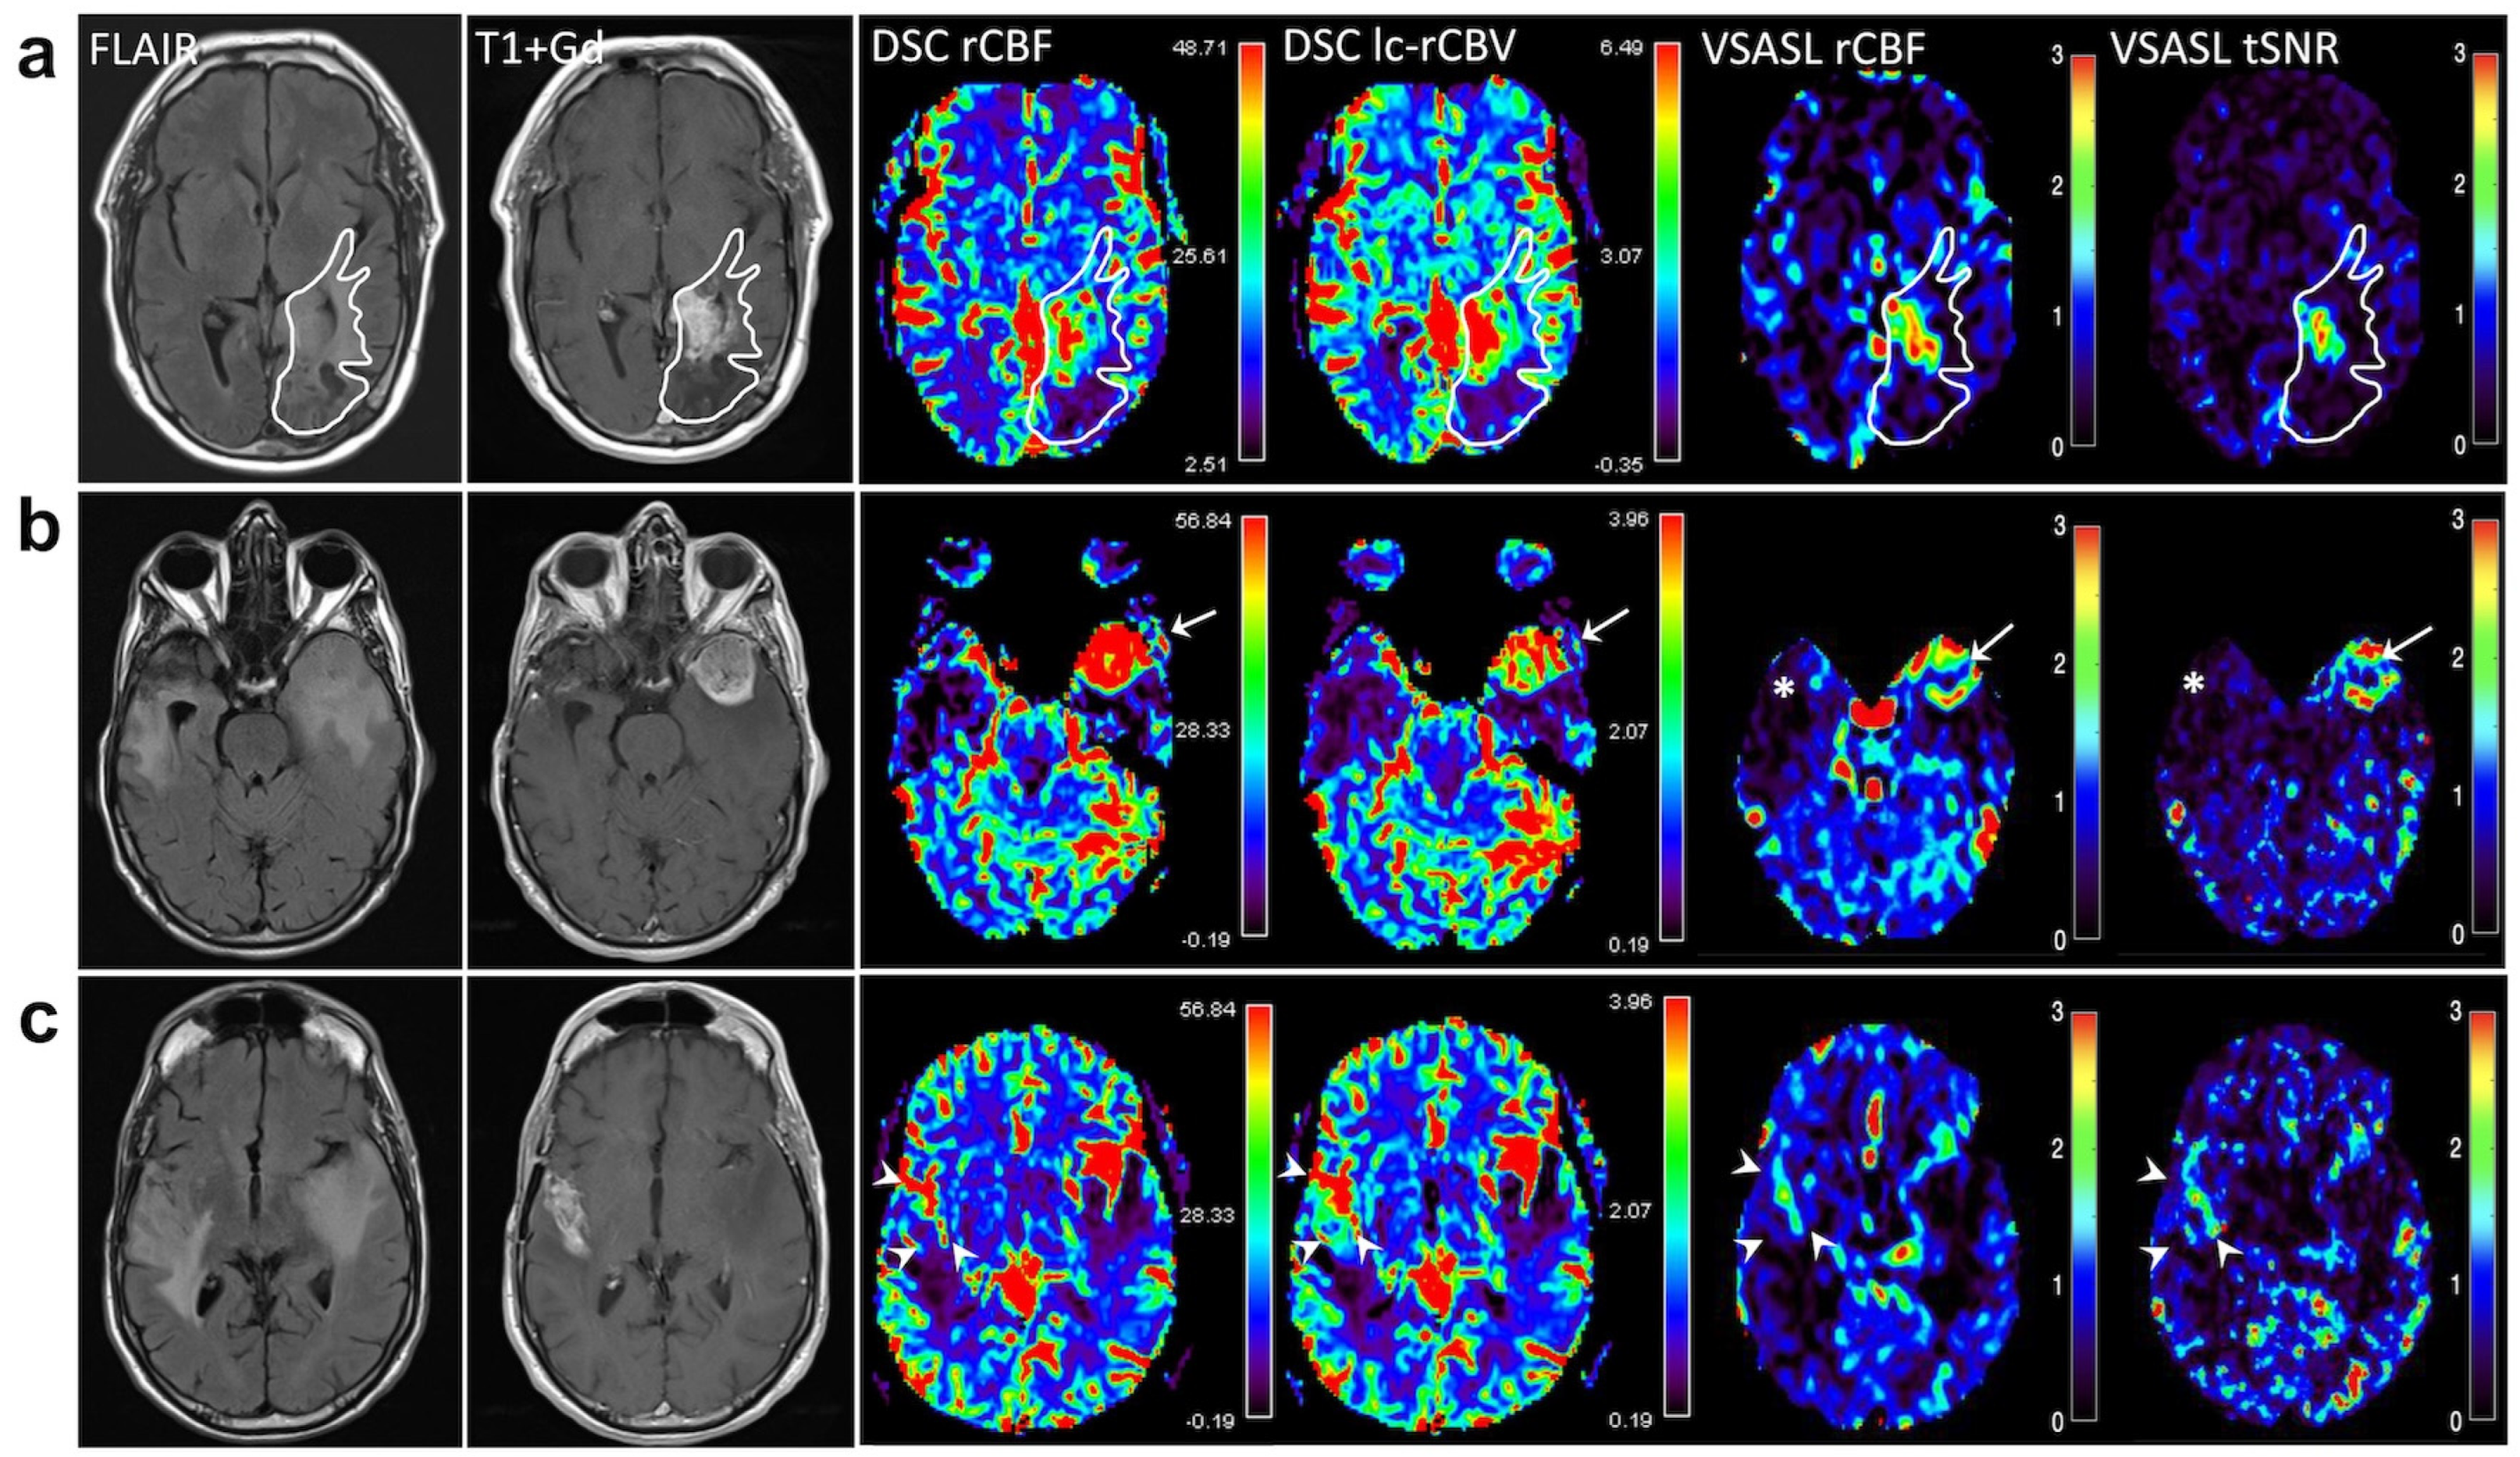

3. Results